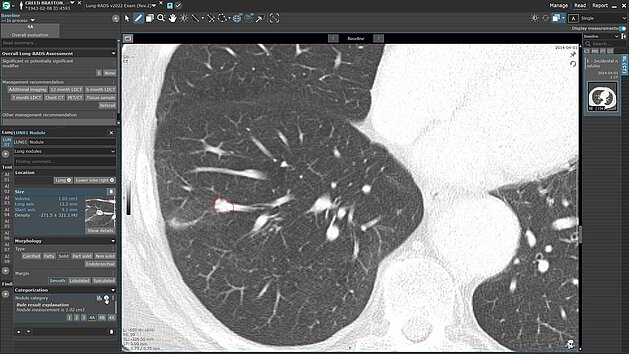

Radiologist creating a structured report with mint Lesion software

Structured reporting is redefining radiology by standardizing documentation, enhancing clarity, and generating data ready for clinical use and AI applications. With mint Lesion, radiologists can work efficiently while producing high-quality, interoperable data that support diagnostics, research, and patient outcomes.

Leverage Advanced AI-Driven Nodule Detection and Analysis for Comprehensive Patient Care

Discover the power of streamlined AI-driven lung screening with contextflow ADVANCE Chest CT integrated into mint Lesion. With automated lung nodule…